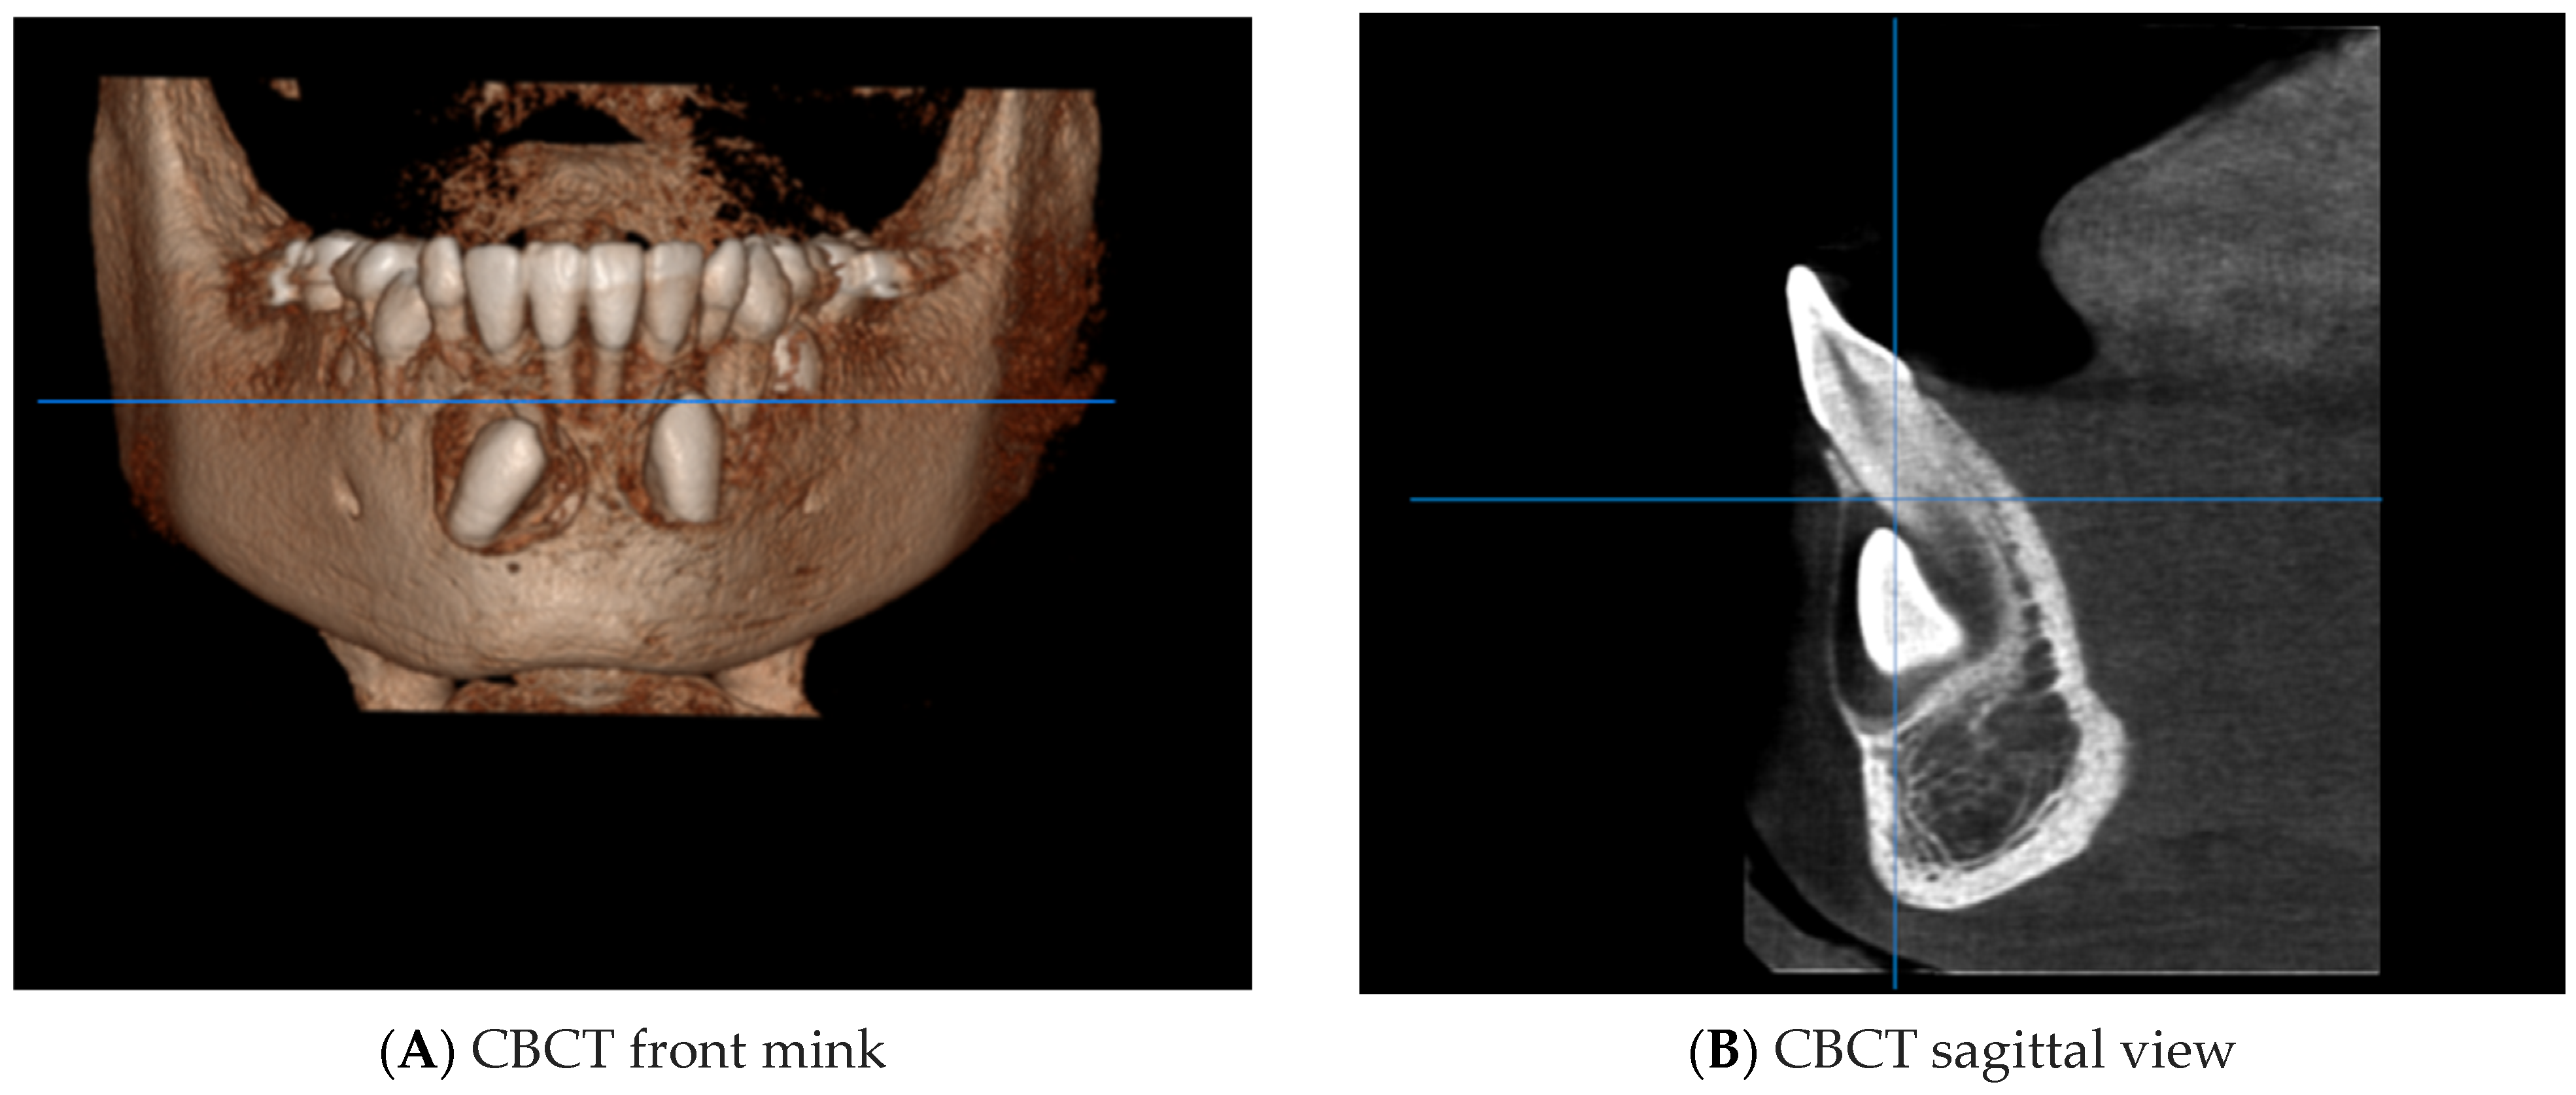

4. Case Report

4.1. Phase 1: Initial Orthodontic Treatment

4.2. Phase 2: Surgical Technique

4.3. Orthodontic Traction

4.4. Phase 3: Final Orthodontic Treatment